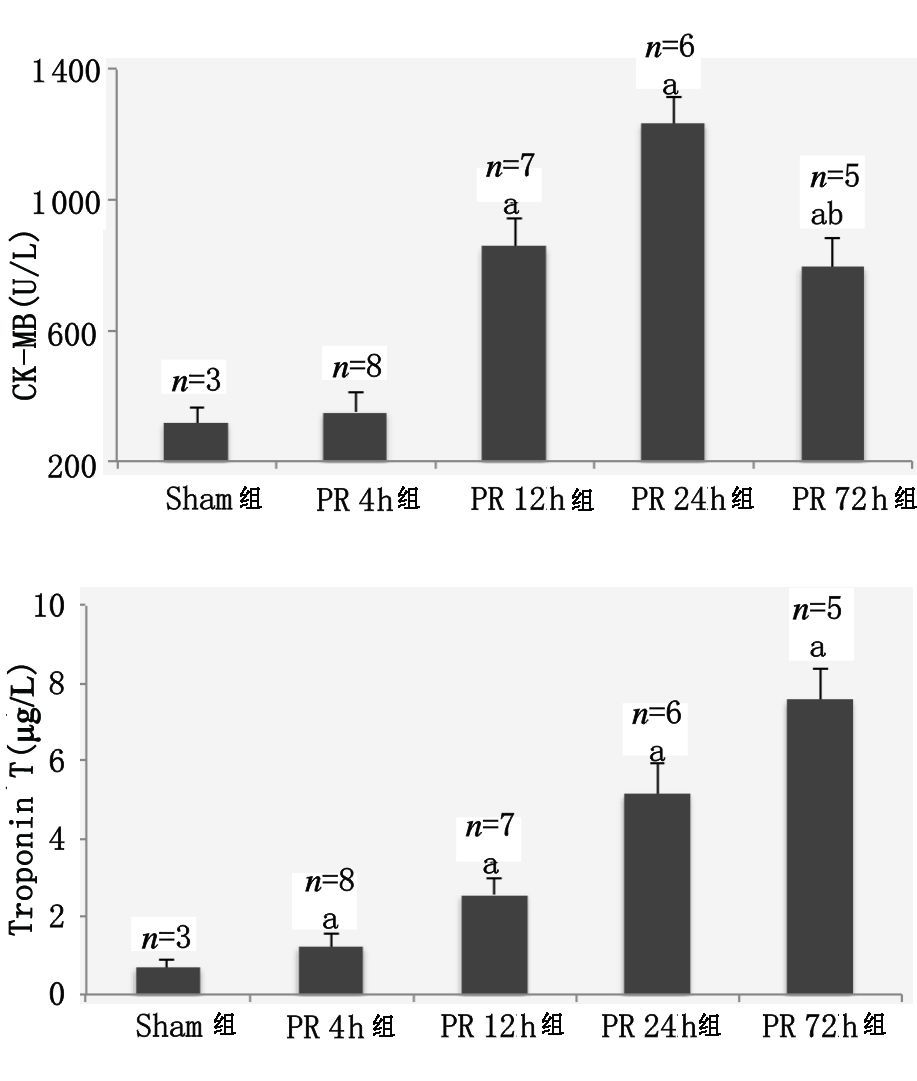

ELISA结果示PR 4 h组与Sham组的CK-MB差异无统计学意义(P>0.05) ;PR 12 h组和PR 24 h组的CK-MB高于Sham组(P<0.05) ;PR 72 h组的CK-MB下降,但仍高于Sham组(P<0.05) 。复苏后各时间点的troponin I逐步增加,均高于sham组(均P<0.05) ,见图 1。

| 指标采用均数±标准差(x±s)表示;与sham组比较,aP<0.05;与PR 24 h组比较,bP<0.05 图 1 血清CK-MB、troponin I动态变化 Figure 1 Dynamic changes of serum CK-MB and troponin I |